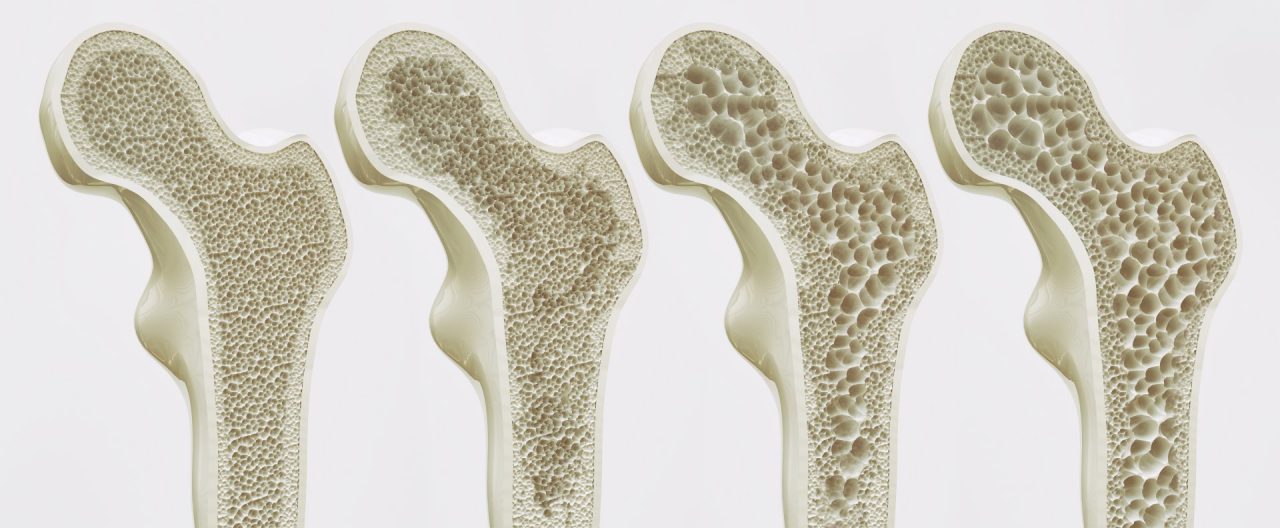

L’osteoporosi è una malattia sistemica delle ossa caratterizzata metabolico che si caratterizza dalla riduzione della massa ossea e nonché dal deterioramento della sua architettura del tessuto.

Non a caso il nome della patologia significa “osso poroso”; le alterazioni ossee possono esser causa di una maggiore fragilità dell’osso che può fratturarsi a seguito di un trauma a bassa energia e nei casi più gravi nell’esecuzione di semplici movimenti o in seguito al sollevamento di pesi anche leggeri.

L’indagine densitometrica consente di misurare la massa ossea ed in particolare la sua densita` minerale (bone mineral densityometry BMD) in g/cm2 di superfice ossea proiettata.

La BMD è responsabile della resistenza meccanica dell’osso per il 60-80%.

Per l’OMS la diagnosi densitometrica di osteoporosi si basa sulla valutazione con tecnica dual-energy x-ray absorptiometry (DEXA) della densita` minerale, raffrontata a quella media di soggetti adulti sani (Picco di massa ossea). L’unita` di misura è rappresentata dalla deviazione standard dal picco medio di massa ossea (T-score).

E` stato osservato che il rischio di frattura inizia ad aumentare in maniera esponenziale con valori densitometrici di T-score<-2.5 deviazione standard (DS) che, secondo l’OMS, rappresenta la soglia per diagnosticare

1) la BMD normale e` definita da un T-score compreso fra +2,5 e -1,0 DS; 2) l’osteopenia (bassa BMD) e` definita ad un T-score compreso tra -1,0 e -2,5 DS; 3) l’osteoporosi e` definita da un T-score inferiore a -2,5 DS; 4) l’osteoporosi conclamata e` definita da un T-score inferiore a -2,5 DS e dalla contemporanea presenza di una o piu` fratture da fragilita`.